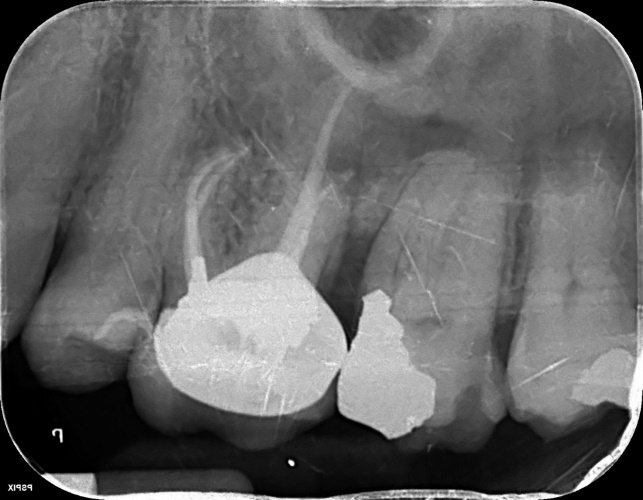

Lower Molar x2 curved roots Primary Root canal treatment and dental crown/rebuild